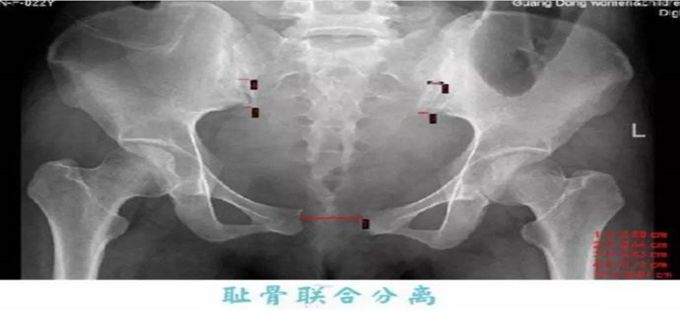

3、影像学检查

超声检查:孕期常采用 B 超测量:耻骨联合缝隙宽>10mm,左右错合差度≥5mm;

影像学X线片见耻骨联合缝隙宽>10mm 。(正常人耻骨间隙为4~6mm,孕期可增宽2~3mm。一般认为耻骨联合间隙超过10mm可确诊。)